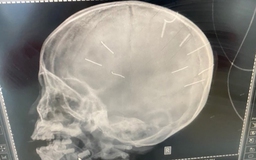

Tìm thấy 10 chiếc đinh trong đầu bé gái bị người tình của mẹ bạo hành

Bé gái bị nhân tình của mẹ đóng 9 chiếc đinh vào đầu đã tử vong